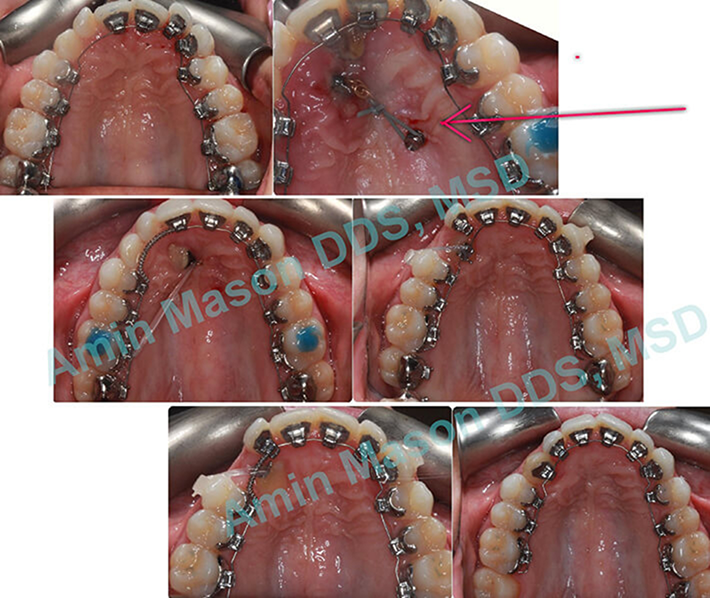

TADs Used To Guide Impacted Canines

Adult patient impacted tooth in the palate. TAD in palate was used to guide the canine into the arch.

TADs Used to Correct Open Bite Malocclusion Non-Surgically

Teenage patient with open bite malocclusion. Two TADs were used to close the bite.